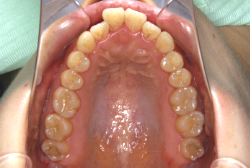

混合歯列期から治療開始した側方拡大による非抜歯症例

「配列の凸凹を治したい」という主訴で来院したケースです。診断の結果、永久歯がすべて生えそろうと、かなり厳しい叢生(歯並びの凸凹のことです)になる可能性が高いと判明しました。原因としては特に上の顎の骨が小さいため、歯を収容する容量不足になっていると診断しました。このケースの場合は、成長発育期に治療開始しますので、顎の骨を土台ごと大きくすることが可能です。

そこで、まず急速拡大装置を使用して上顎骨の拡大を行い、上顎骨の容量が拡大したことを確認後、マルチブラケット装置を使って全体の修正をする、と言う二段階の作戦をとることになりました。

この時期に使う急速拡大装置は、適切な診断に基づいて正しく使用することで確実に骨を大きくすることができます。拡大することで隙間が確保できるので、永久歯の抜歯を避けることができます。

急速拡大装置を1日1回装置の中央にある拡大ネジを、ご自身で回して頂くことで25日間くらいかけて、6mmほど拡大しました。拡大後は、上顎の前歯の隙間が広がっていることがお分かりいただけると思うのですが、土台の骨ごと広がるのでこのような隙間ができます。その後1年半くらいマルチブラケット装置を使用して、全体の修正を行いました。

結局、歯の本数を減らすことなく、すべてご自分の歯を残して正しい配列にすることができました。このケースの場合、2009年10月より拡大と経過観察を行い、2012年3月より1年2ヶ月マルチブラケット装置を装着、2013年5月に治療を終了しました。2段階で行う治療としては短期間で終了しているケースと思います。